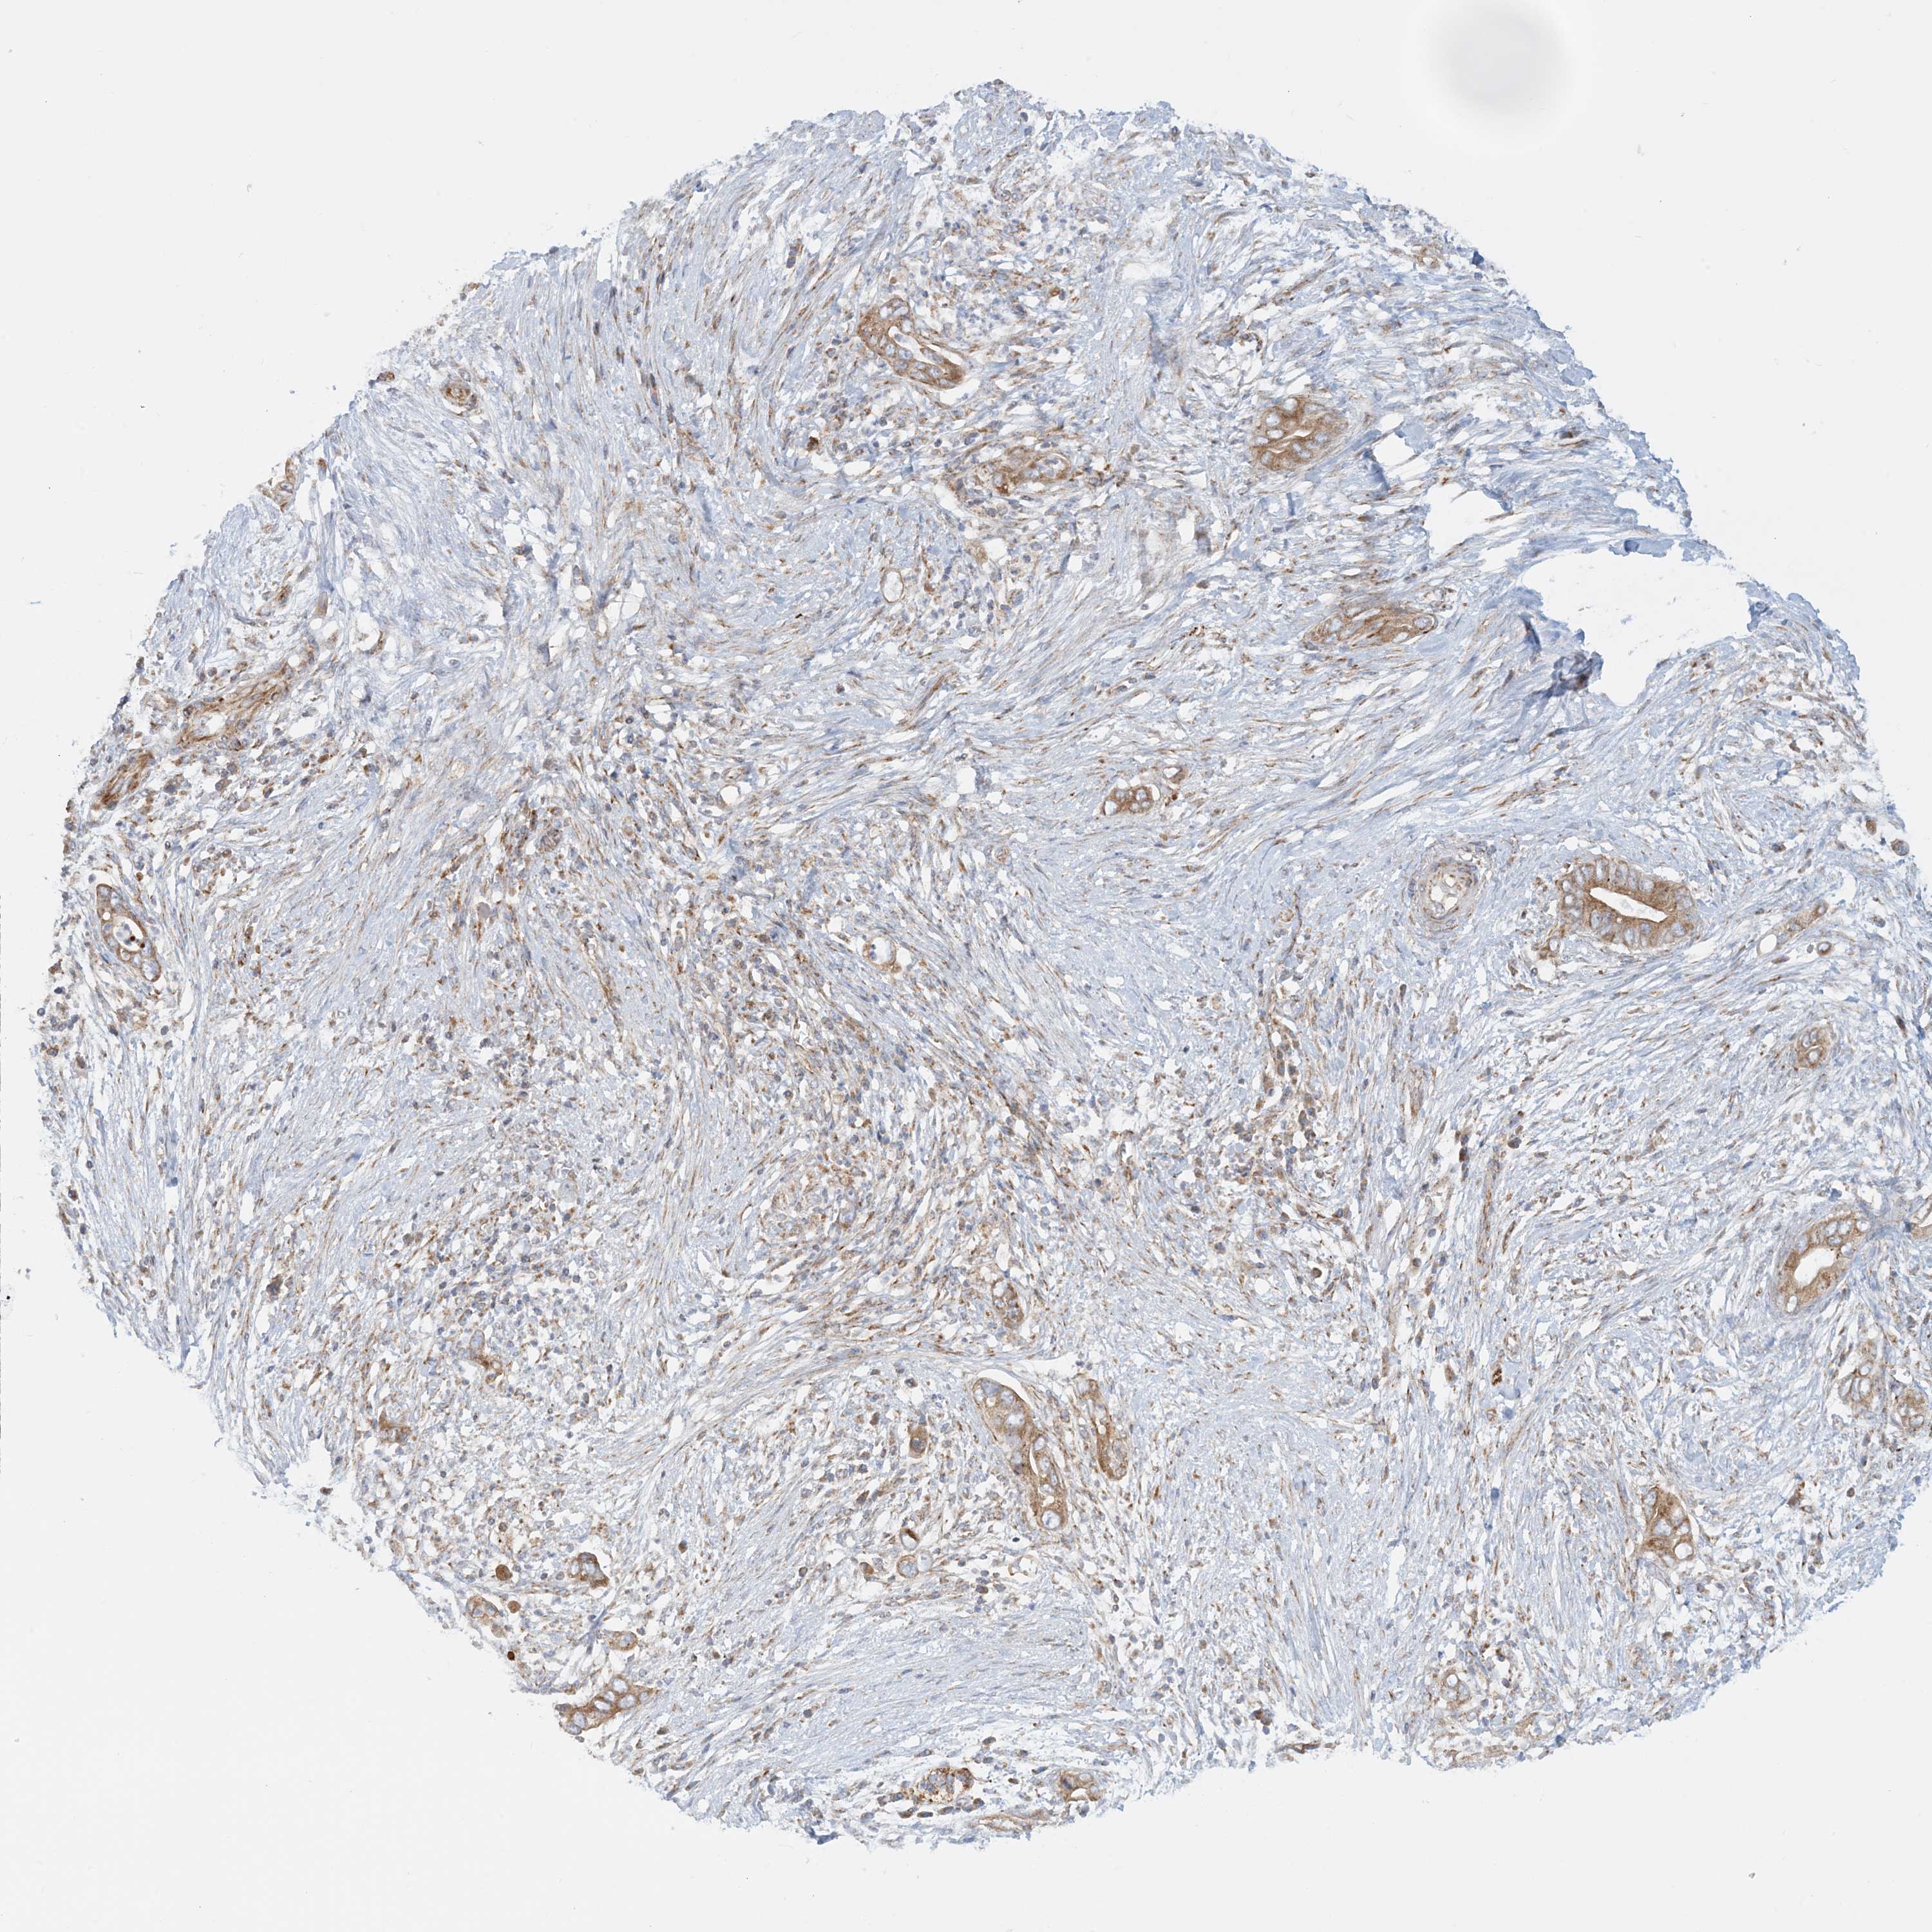

PANCREATIC CANCER - Protein expressioni

A mouse-over function shows sample information and annotation data. Click on an image to view it in a full screen mode. Samples can be filtered based on level of antibody staining by selecting one or several of the following categories: high, medium, low and not detected. The assay and annotation is described here.

Note that samples used for immunohistochemistry by the Human Protein Atlas do not correspond to samples in the TCGA dataset.

Antibody stainingi

Antibody staining in the annotated cell types in the current human tissue is reported as not detected, low, medium, or high, based on conventional immunohistochemistry profiling in selected tissues. This score is based on the combination of the staining intensity and fraction of stained cells.

Each image is clickable and will lead to virtual microscopy that enables deeper exploration of all samples and also displays staining intensity scores, fraction scores and subcellular localization as well as patient and tissue information for each sample.

Antibody HPA031966

Staining

High

Medium

Low

Not detected

Intensity

Strong

Moderate

Weak

Negative

Quantity

>75%

75%-25%

<25%

None

Location

Nuclear

Cytoplasmic/membranous

Cytoplasmic/membranous,nuclear

Adenocarcinoma, NOS